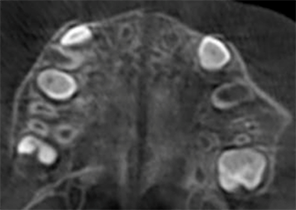

Case Report 2

7 years 11 months old, 24 stages of Invisalign® Palatal Expanders

Courtesy of Dr. David R. Boschken

Pre Invisalign Palatal Expander Expansion

Post Invisalign Palatal Expander Expansion

Post Invisalign Palatal Expander Treatment